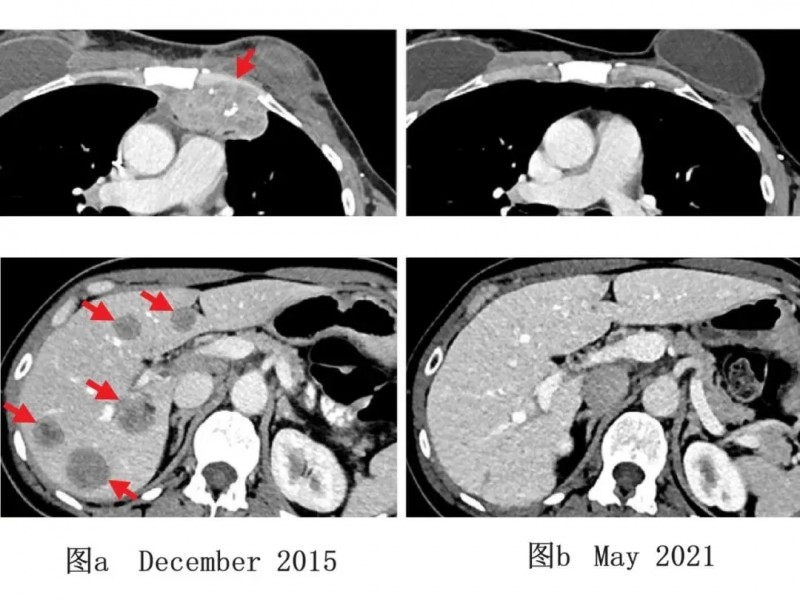

核心疗效数据亮眼:50%(3/6)患者实现可测量肿瘤缩小,其中1例达成持续无癌生存,另外2例在治疗后6个月、10个月的肿瘤缩小率分别达52%和69%。更值得关注的是,所有患者随访3.5年至5年,均无新发癌症。

1例乳腺癌典型病例TIL治疗前后的影像学对比图,更是直观印证了治疗效果:2015年12月检查显示,该患者肝脏及胸壁存在转移性病灶(详见下图a);经该免疫联合治疗后,2021年5月影像学检查证实肿瘤完全消退,且5年随访期间未出现复发(详见下图b)。该研究为转移性乳腺癌的免疫联合治疗策略提供了关键临床依据。